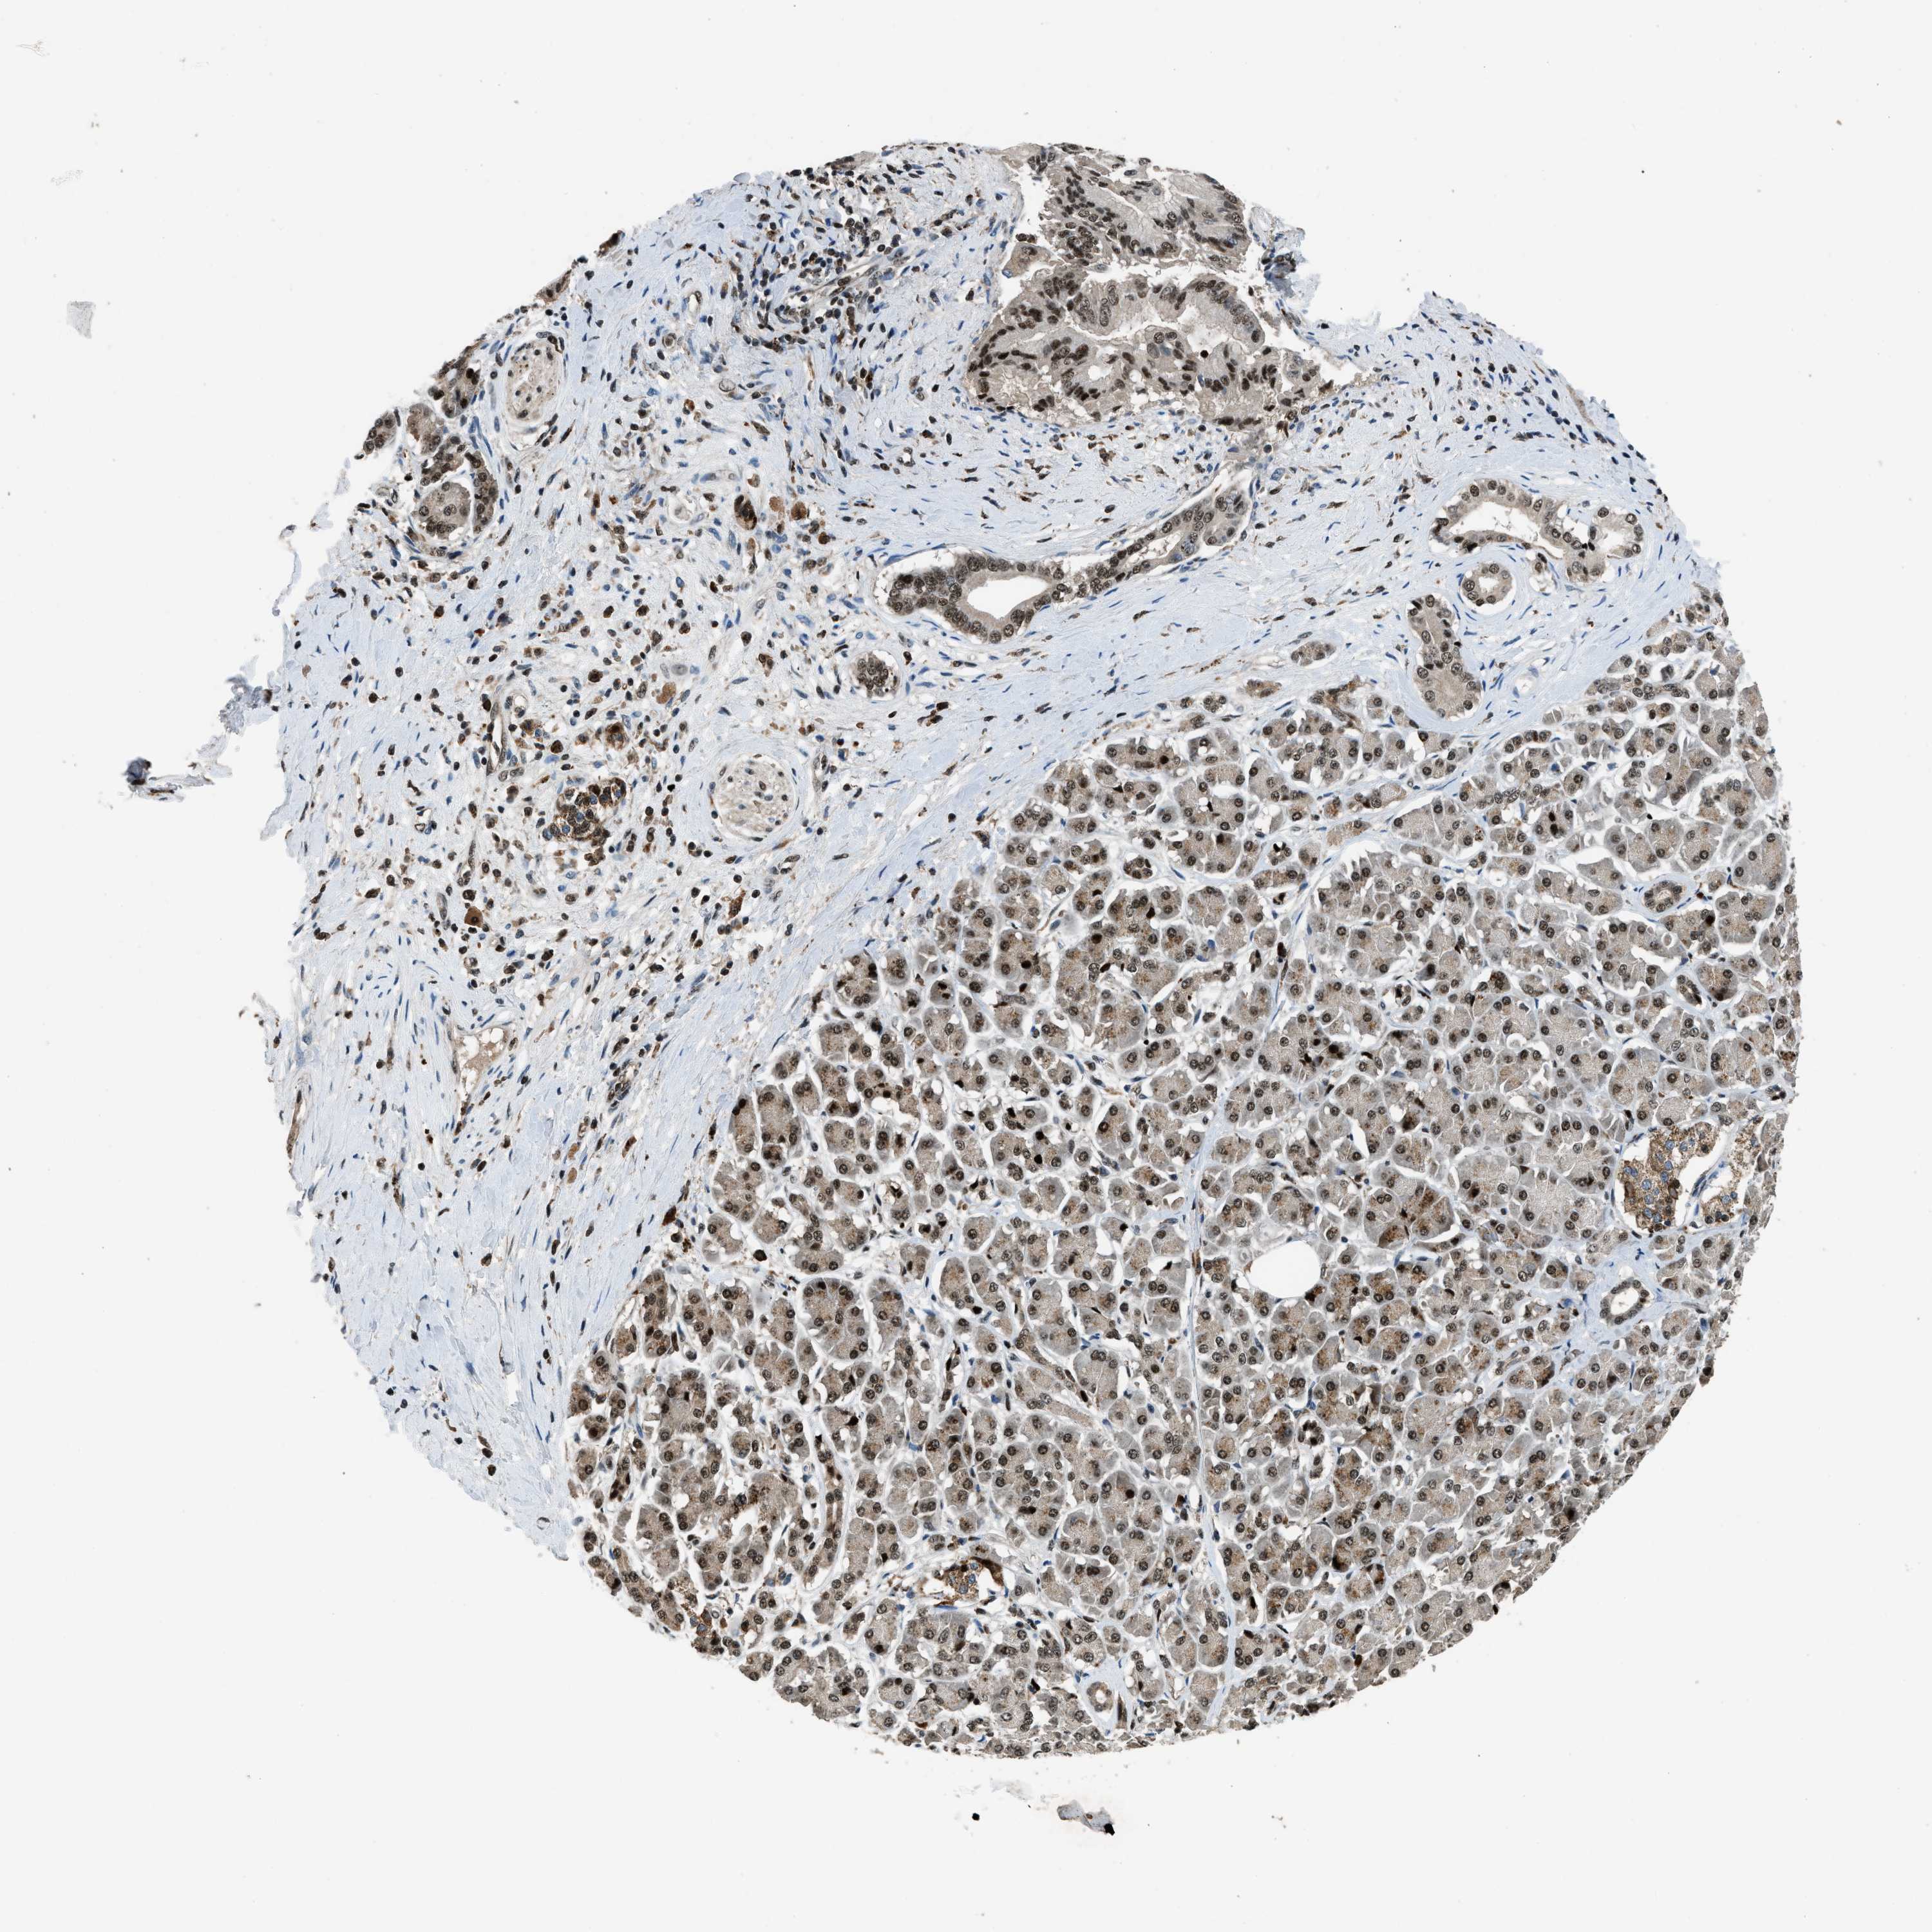

PANCREATIC CANCER - Protein expressioni

A mouse-over function shows sample information and annotation data. Click on an image to view it in a full screen mode. Samples can be filtered based on level of antibody staining by selecting one or several of the following categories: high, medium, low and not detected. The assay and annotation is described here.

Note that samples used for immunohistochemistry by the Human Protein Atlas do not correspond to samples in the TCGA dataset.

Antibody stainingi

Antibody staining in the annotated cell types in the current human tissue is reported as not detected, low, medium, or high, based on conventional immunohistochemistry profiling in selected tissues. This score is based on the combination of the staining intensity and fraction of stained cells.

Each image is clickable and will lead to virtual microscopy that enables deeper exploration of all samples and also displays staining intensity scores, fraction scores and subcellular localization as well as patient and tissue information for each sample.

Antibody HPA016713

Staining

High

Medium

Low

Not detected

Intensity

Strong

Moderate

Weak

Negative

Quantity

>75%

75%-25%

<25%

None

Location

Nuclear

Cytoplasmic/membranous

Cytoplasmic/membranous,nuclear

Adenocarcinoma, NOS